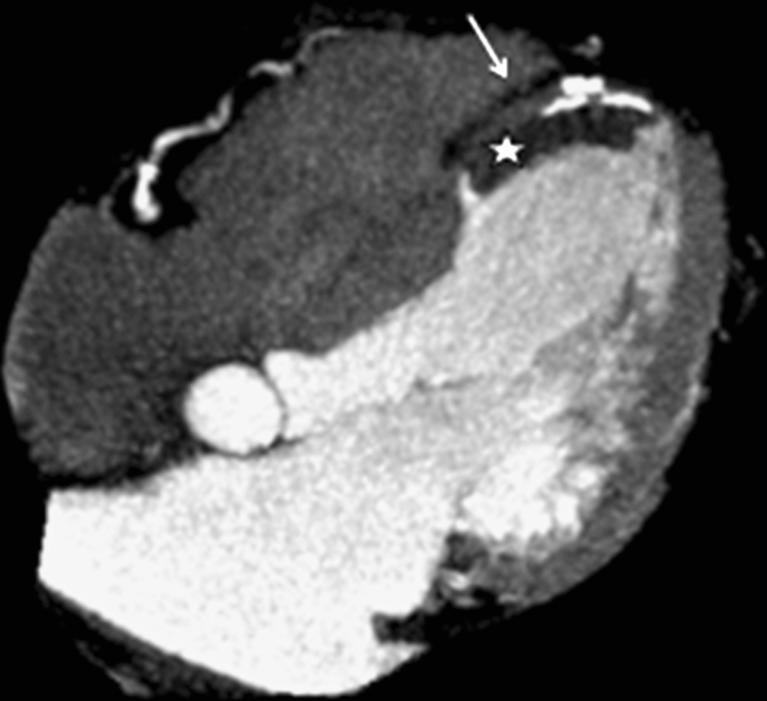

Left ventricular apical diseases.

There are many disorders that may involve the left ventricular (LV) apex; however, they are sometimes difficult to differentiate. In this setting cardiac imaging methods can provide the clue to obtaining the diagnosis. The purpose of this review is to illustrate the spectrum of diseases that most frequently affect the apex of the LV including Tako-Tsubo cardiomyopathy, LV aneurysms and pseudoaneurysms, apical diverticula, apical ventricular remodelling, apical hypertrophic cardiomyopathy, LV non-compaction, arrhythmogenic right ventricular dysplasia with LV involvement and LV false tendons, with an emphasis on the diagnostic criteria and imaging features. ELECTRONIC SUPPLEMENTARY MATERIAL: The online version of this article (doi:10.1007/s13244-011-0091-6) contains supplementary material, which is available to authorized users.